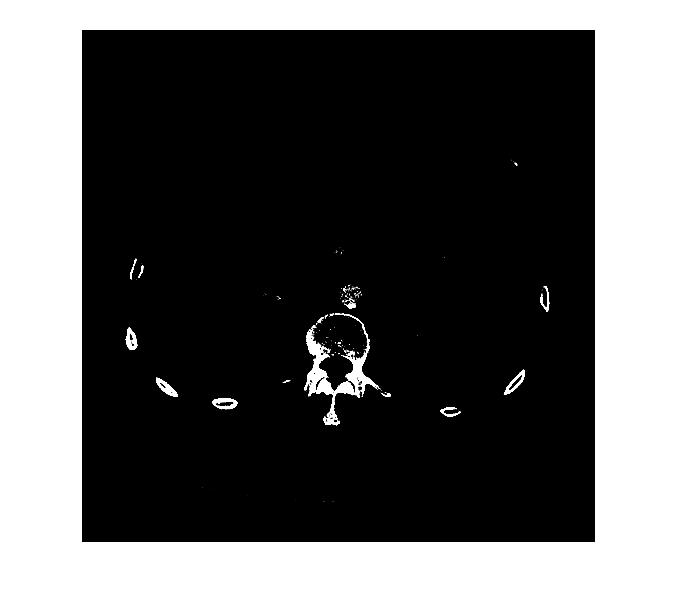

meine Aufgaben sind Segmention von den Knochen,bzw die Rippen, von den CTsbilder

habe versucht und habe herausgefunden,dass die Knochen werte leigen zwischen 1250 und 1300,,Bildkontrast,,

aber ich treffe ein parr Gefäße im Bild,,die ich ausschalten muss

hat jemanden eine Idee,wie ich die ausschalten muss